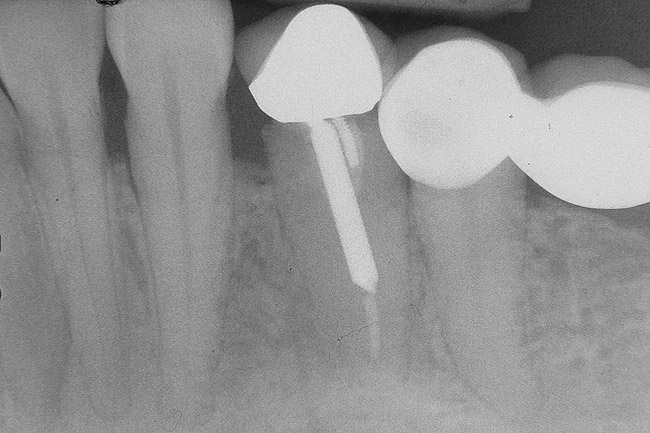

Figure 9  Extraction of teeth Nos. 29 and 31 with immediate implants (Straumann USA, Waltham, MA) placed into the site.

Figure 9

Figure 10  Implants seen in Figure 9 restored approximately 3 months after placement.

Figure 10